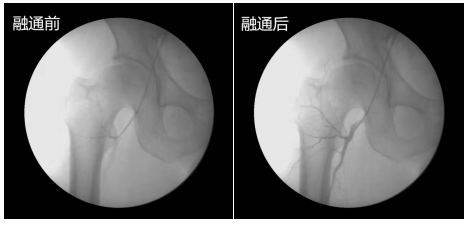

治疗与疾病的对抗,好比在战争中敌我双方始终处于胶着状态你来我往反复不断。大多数患者只想到了病情反复,却完全没想到到底为何会出现这样的问题。据调查显示70%的患者都只在乎治疗,从而忽视了检查这一重点。 在战争中讲究的是知己知彼,方能百战百胜。那么我们在治疗疾病时,不清楚病因病情能治好疾病吗?当然不能!所以我们在治疗股骨头坏死时,首先要查明病根是什么,股骨头坏死是怎么发生的。 作为一种常见的骨科顽疾,临床已经证实:其根本致病原因在于股骨头三大供血动脉血管堵塞引起的血供中断,而股骨头血供与人体其他骨头不一样,它只有三根细小的血管供应,如果其中一根或者多根血管堵塞了,导致股骨头局部血运不良,从而引起骨细胞缺血与坏死、骨小梁断裂、股骨头塌陷等一系列病变的发生。 因此股骨头坏死的鉴别诊断以及保髋治疗的关键都在于是否能够有效融通堵塞血管,改善股骨头周围血运,阻断坏死机制。 >>>你知道治疗股骨头坏死,需要做足哪些专业检查吗?点击了解 血管融通是目前治疗股骨头缺血性坏死公认的最好的技术,已成为业内专家学者和股骨头坏死患者本人的共识,然而并非所有血管融通都能保住股骨头不置换,一方面,一些非专业的医院融通技术尚未成熟,另一方面,股骨头坏死任何有效治疗都是建立在科学检查的基础之上。回顾患者求医历程,不难发现:无论是基层医院还是三甲医院,都是存在着“重治不重诊”,医生给出的方案基本千篇一律,“诊”这一步出了问题,那么后续的治疗也就无从考究,盲目治疗的结果必然是病情反复。 应用可视血循分析仪,主要用于血管堵塞、堵塞的原因及程度的检测,通过可视追踪造影、四维成像技术,检查出股骨头三大供血动脉发生血堵的位置、栓塞种类以及堵塞程度,了解股骨头缺血的病因,为融通血管靶向治疗提供更详细数据,弥补常规检查的不足。